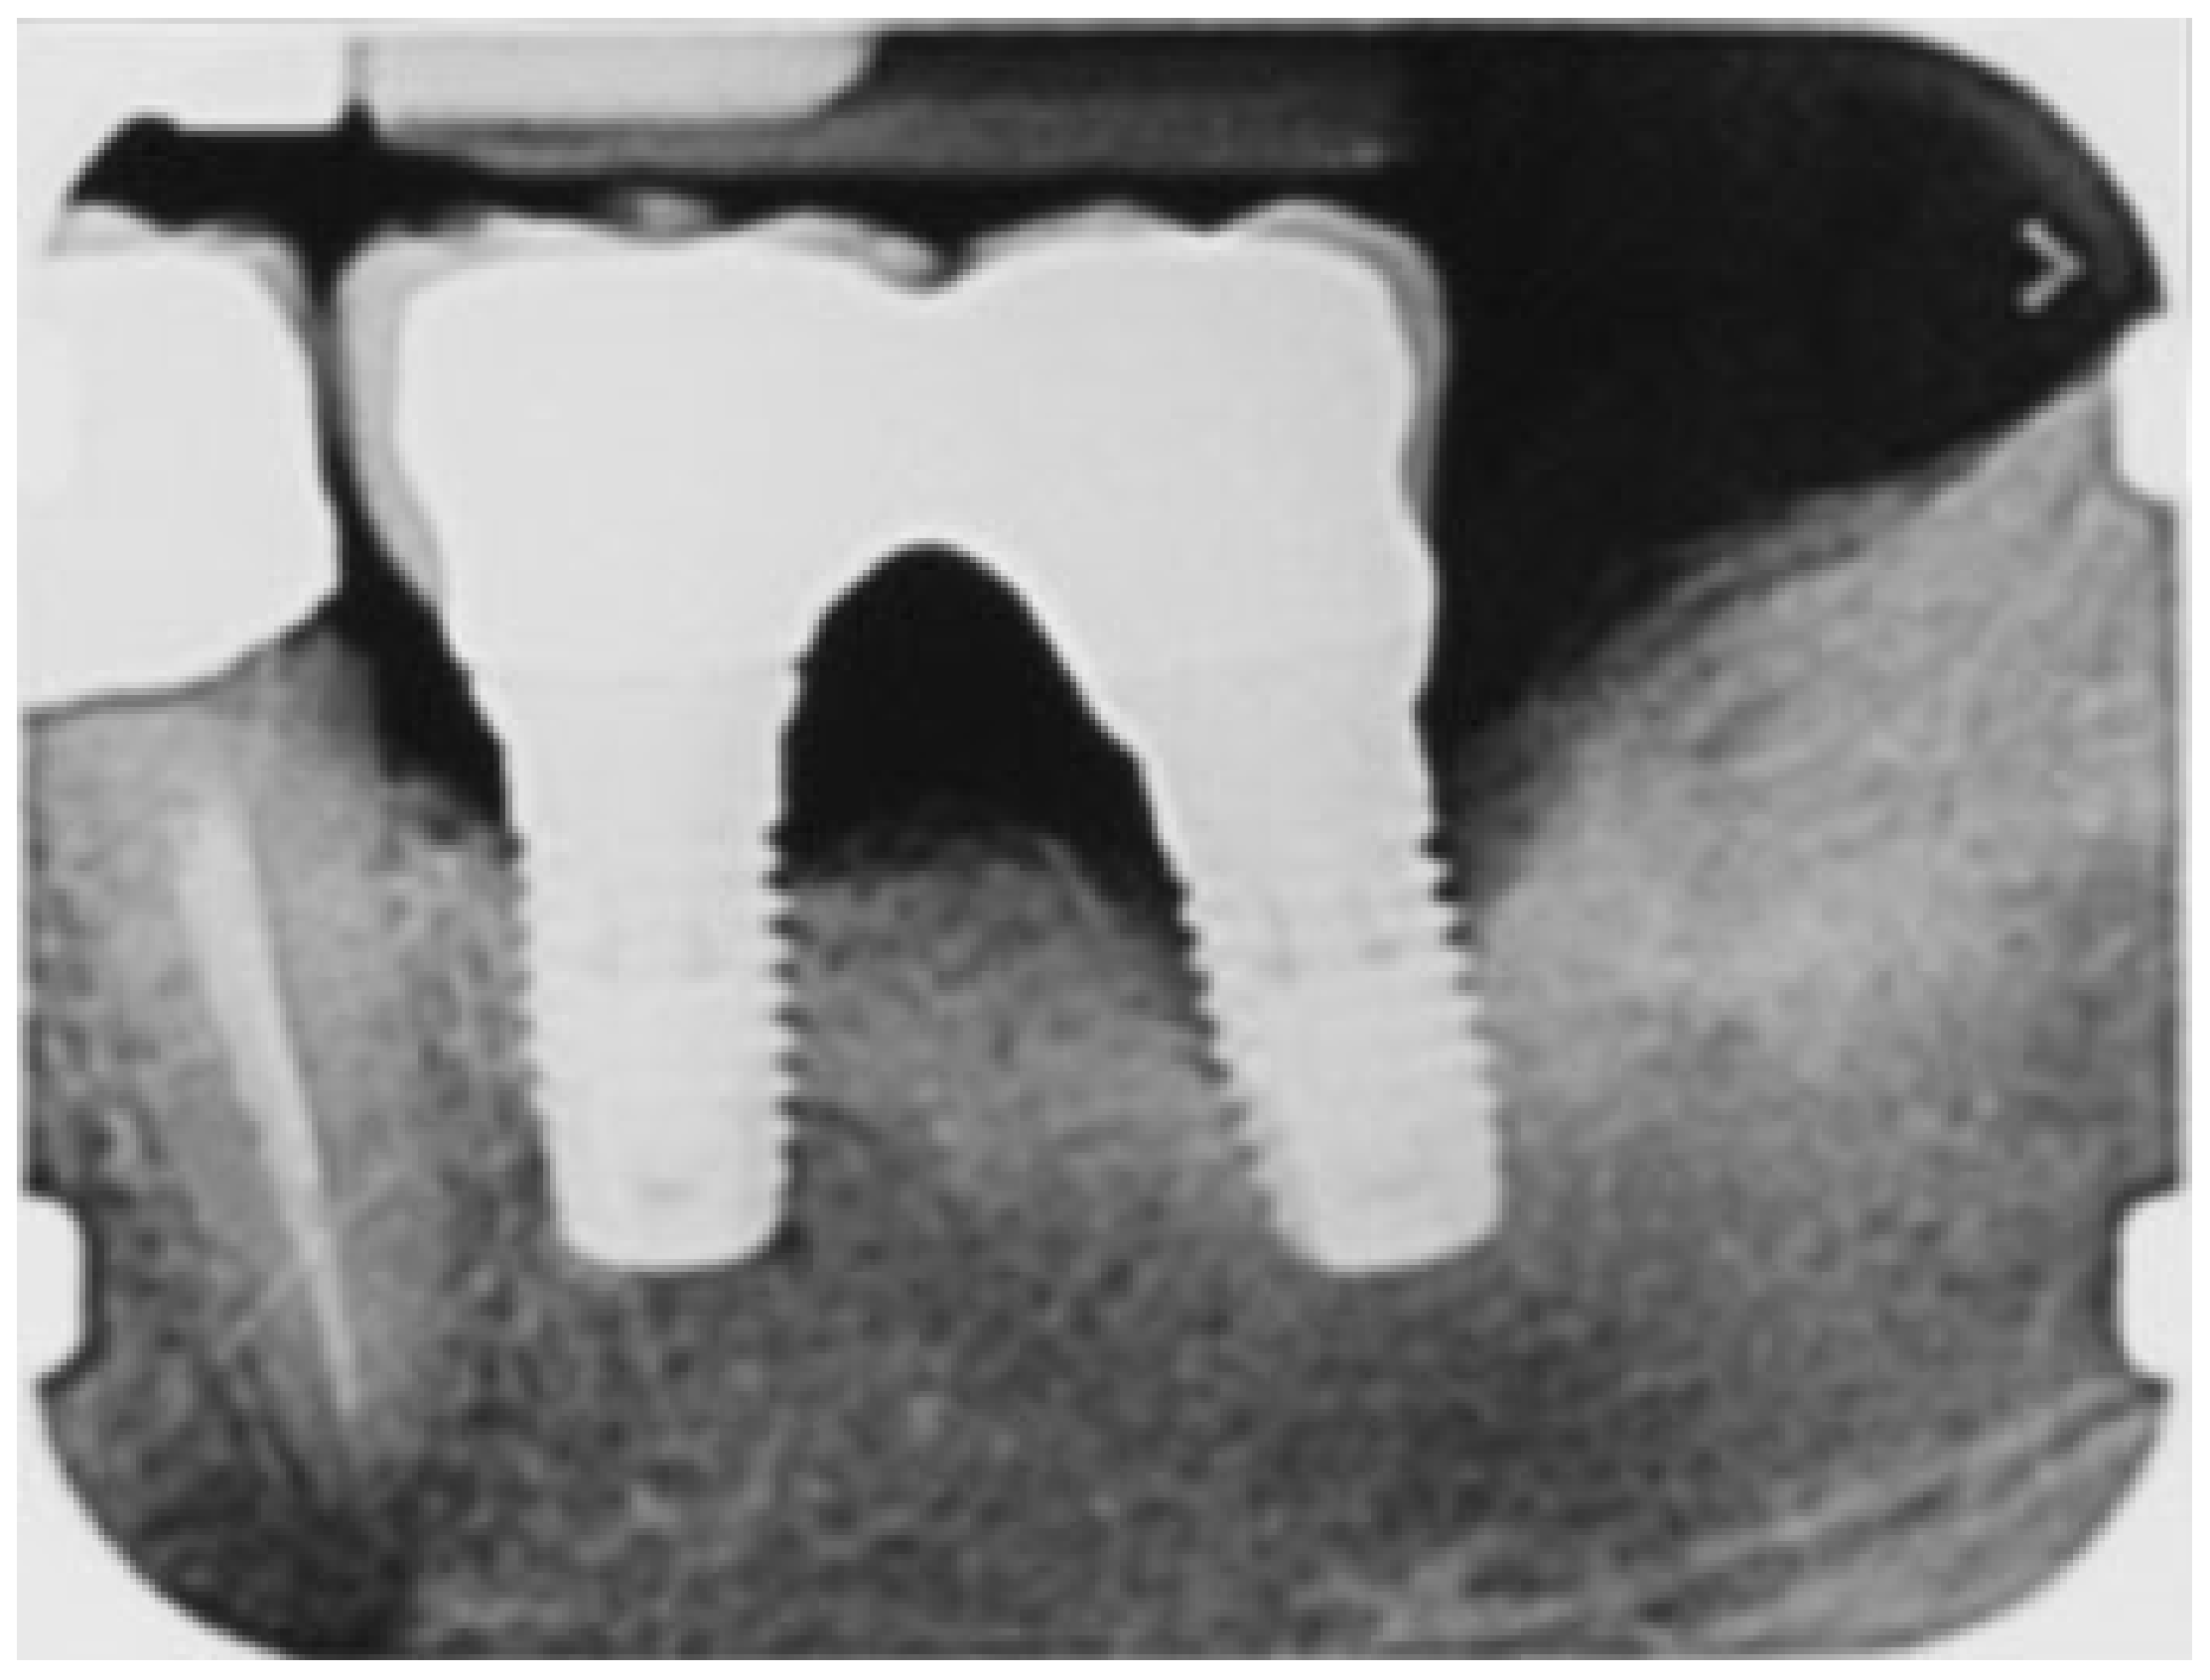

A 65-year-old woman with a noncontributory medical history was referred to the Oral Surgery Unit, Policlinico Umberto I, “Sapienza” University of Rome, Italy, to undergo surgical reconstructive therapy peri-implantitis lesion localized around the mandibular left distal implant (Figure 1 and Figure 2). The patient’s written detailed informed consent was obtained for the diagnostic and therapeutic approach and the use of the documentation for research purposes and publishing.

Figure 2. Rx periapical before peri-implant therapy: infra-bony defect around the distal implant.